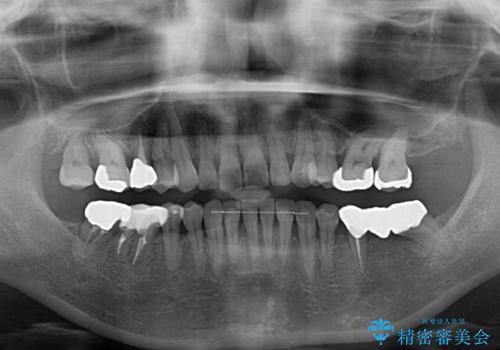

- 飛び出した上顎前歯と正中のズレを気にして来院された患者様です。

上顎正中が右側にずれていたので、むし歯が酷く抜歯が必要な左側臼歯を抜歯して正中を改善することとしました。

左下には新しいセラミックのブリッジが装着されていたため、ブリッジを壊さずに改善できるところまで咬み合わせを改善していくこととしました。

右上小臼歯は銀歯が装着されており、ワイヤー矯正の装置が装着できないため、事前に仮歯に変えてから矯正治療を行い、その後オールセラミッククラウンにて補綴治療を行いました。